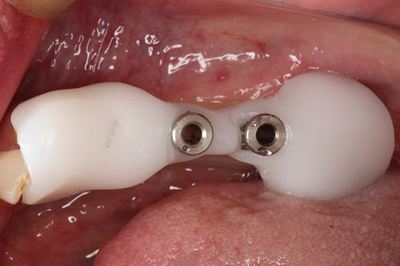

無事埋入を終えました。

インプラント挿入ジグを外しました。

封鎖スクリューを締結し、インプラントフィクスチャーを保護します。